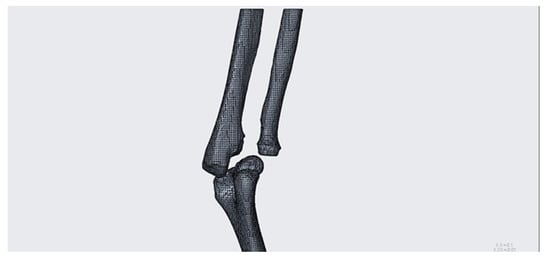

As seen below, to define the references (Figure 7, Figure 8, Figure 9, Figure 10 and Figure 11), complex solids must be approximated to simpler geometries; hence, it will be possible to trace the center planes and points of interest as shown in the figure. Creo allows the selection of each mesh vertex; in this way it can characterize the models in a very precise way and highlight relevant anatomical sections, such as epicondyles or diaphysis axes in long bones.

Figure 7.

Starting model for CREO simulation.

It is important to remember that the features just described (Figure 12, Figure 13 and Figure 14) are only those functional for the simulation of this pathology. The software makes available many other tools that have been used in the processing of the other cases and that will be illustrated in the results chapter.

Figure 12.

(a) View perpendicular to the section built with the related middle planes; (b) perspective view of the same anatomical portion.